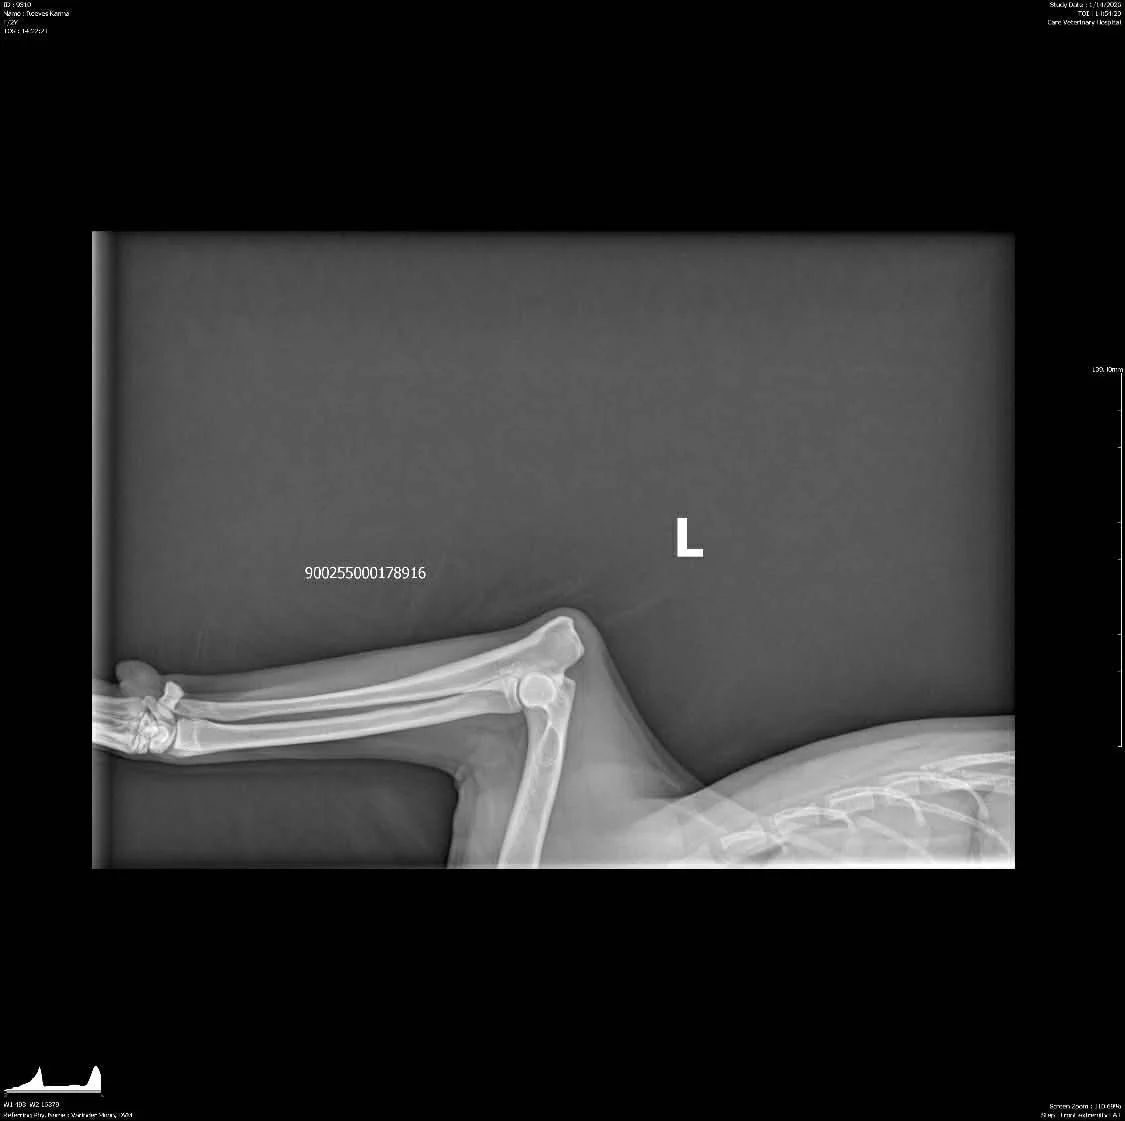

OFA Hips: Clear by parentage, scheduled for fall 2025

OFA Elbows: Clear by parentage, scheduled for fall 2025